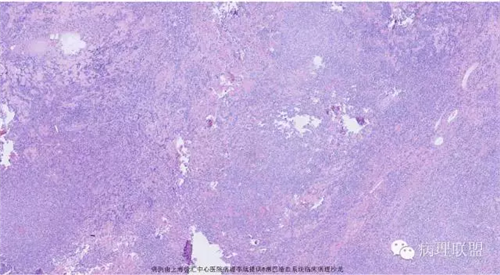

M,79岁,右半结肠粘膜下肿块。大小:6.5*6*6cm球形肿块,切面灰白质硬,界清。第一次取材。